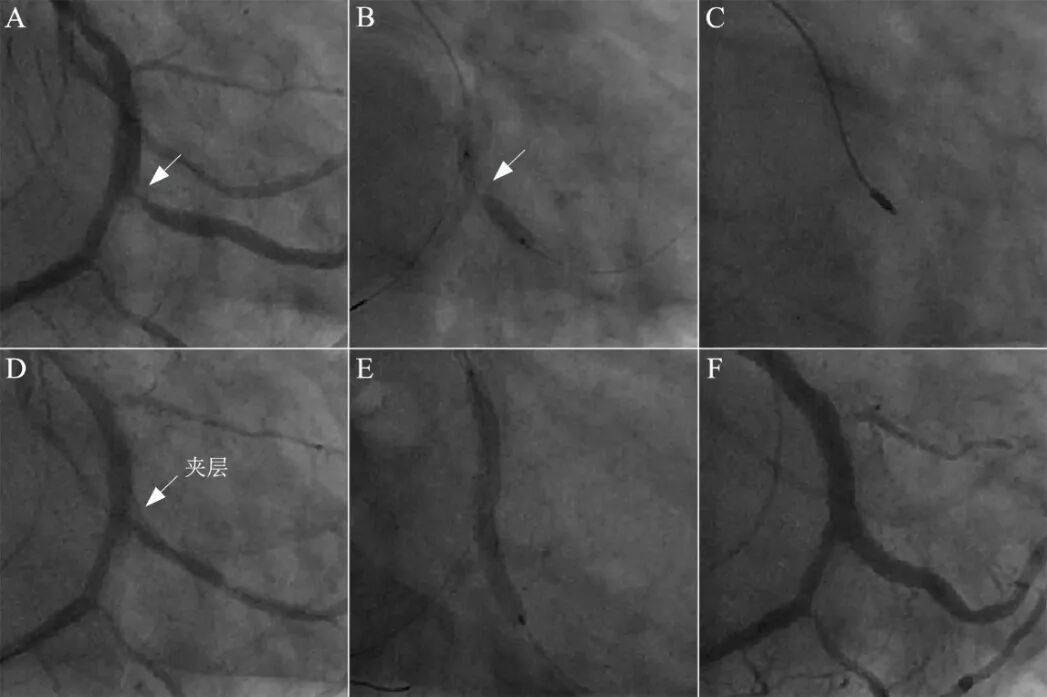

图18 单支架跨越技术处理钝缘支开口病变。

钝缘支开口钙化性狭窄95%(A),球囊16atm膨胀不全(B),启动旋磨治疗,1.25mm磨头尝试3次后顺利通过(C),球囊扩张后可见明显夹层形成(D)。鉴于钝缘支粗大,直接跨越法置入支架(E),结果良好(F)。